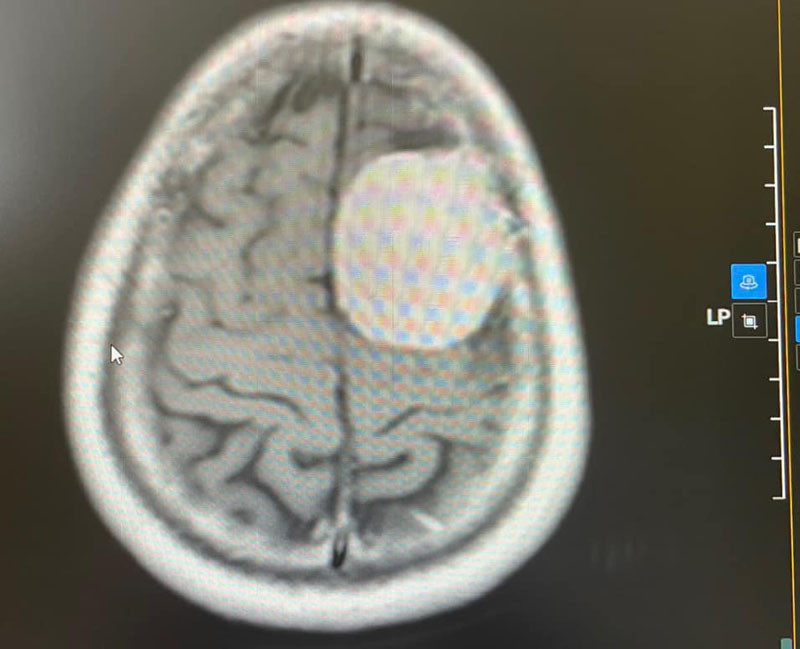

Khối u có kích thước lớn 36x48x52mm vùng trán đỉnh trái của người bệnh

Các bác sĩ đã tiến hành khám và chỉ định chụp cộng hưởng từ có tiêm thuốc cản quang để tìm nguyên nhân và phát hiện khối u kích thước 36x48x54 mm vùng trán đỉnh trái của bệnh nhân. Sau ca phẫu thuật kéo dài hơn 4 giờ, khối u lớn trong não đã được lấy ra trọn vẹn.